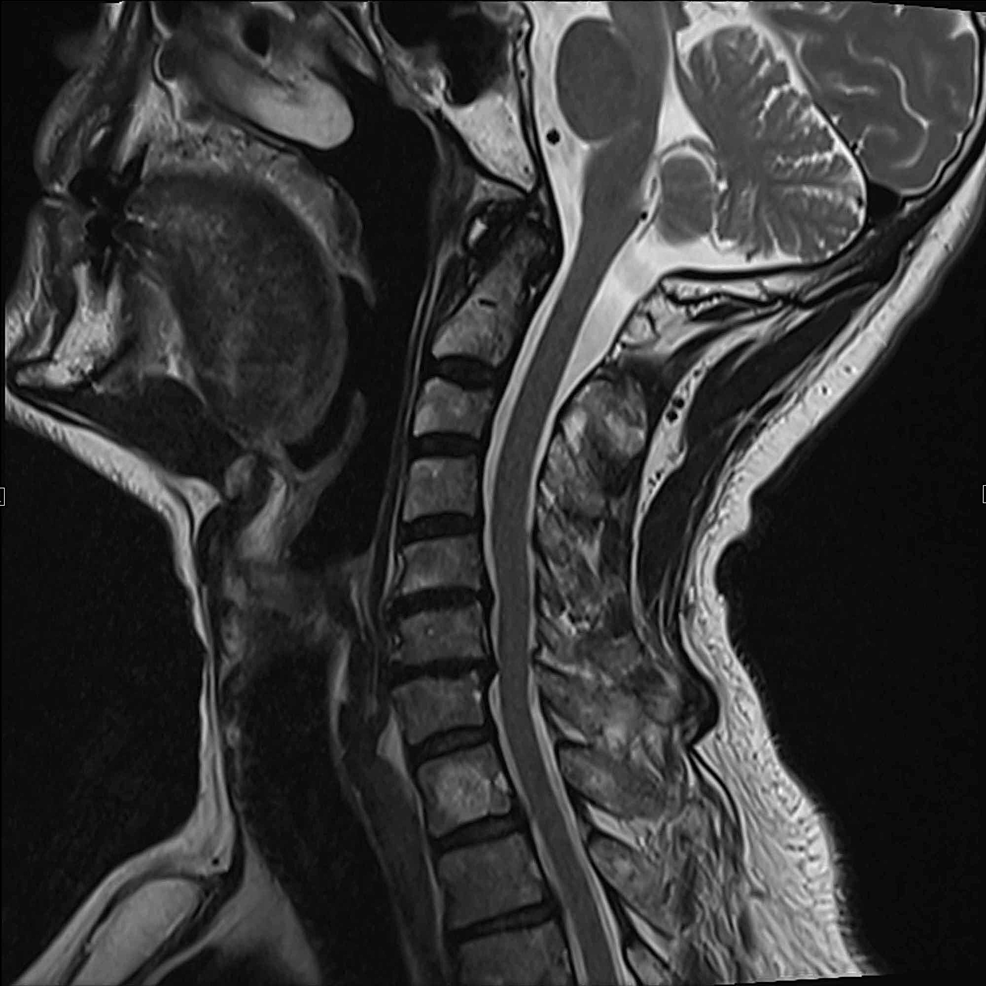

Figure 3 from PostCervical ParsonageTurner Syndrome What Is Turner Parsonage Syndrome Learn about the symptoms, causes, diagnosis, and treatment of pts, a neurological disorder that causes severe shoulder and arm pain and nerve damage. Parsonage turner syndrome (pts) is a rare neurological disorder that causes severe pain and muscle weakness in the shoulder and. It causes sudden pain, weakness, and muscle wasting. Find out how pts can affect different parts of. What Is Turner Parsonage Syndrome.